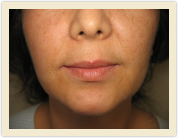

| Before Photo | After Photo |

| Before Photo | After Photo |